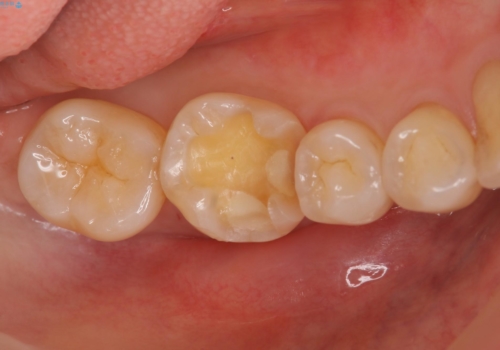

銀歯を白く セラミックインレーに

- 銀歯にしたのが20年以上前とのことで、白くやりかえたいということでした。

セラミックインレーにしています。

- 7万円(左下6 emaxプレスインレー 7万円)費用は治療当時の料金となります

銀歯を外して、下に虫歯があればしっかり取ります。しみるなどの症状が出る前がおすすめです。